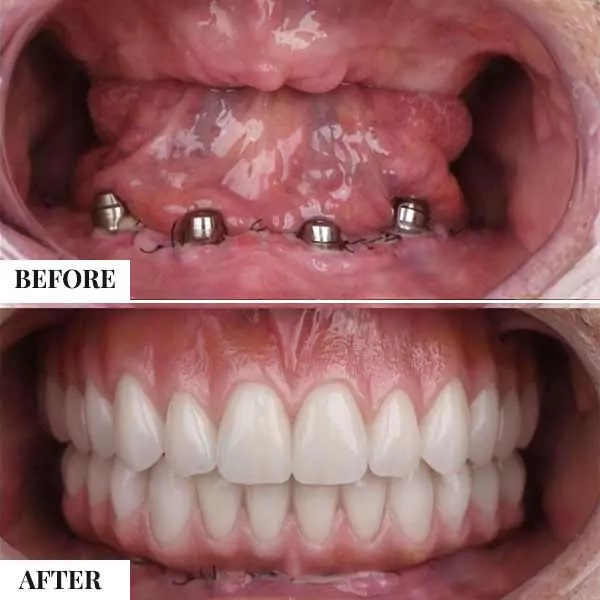

- Immediate Loading Solutions: For qualifying cases, we offer “Immediate Loading” protocols, allowing patients to leave our clinic with functional temporary teeth on the same day as their surgery.

- Solutions for Everyone: Whether you need one tooth replaced or a full set (using All-on-4 or All-on-6 techniques), we have a plan for you.

- Full Arch Rehabilitation: Utilizing All-on-4 or All-on-6 protocols to provide a fixed, non-removable set of teeth for patients missing all teeth in the upper or lower jaw.